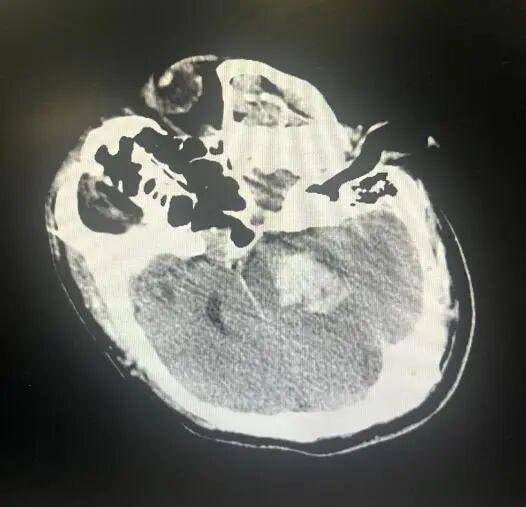

大众卫生报·新湖南客户端12月15日讯(通讯员 罗超)12月初的一天下午,急救车的警报声刺破了寂静。一名中年男性患者被推进了邵阳市中心医院神经重症病房,患者已陷入深度昏迷,针尖样瞳孔,面色发绀,自主呼吸已近乎停止。头部CT影像上,脑干区域那一团一颗葡萄大小的出血灶(约8毫升),却让所有在场医生面色凝重。这不是普通的脑出血,脑干出血8毫升,是一个被医学教科书被标注为“高死亡率”的数值。